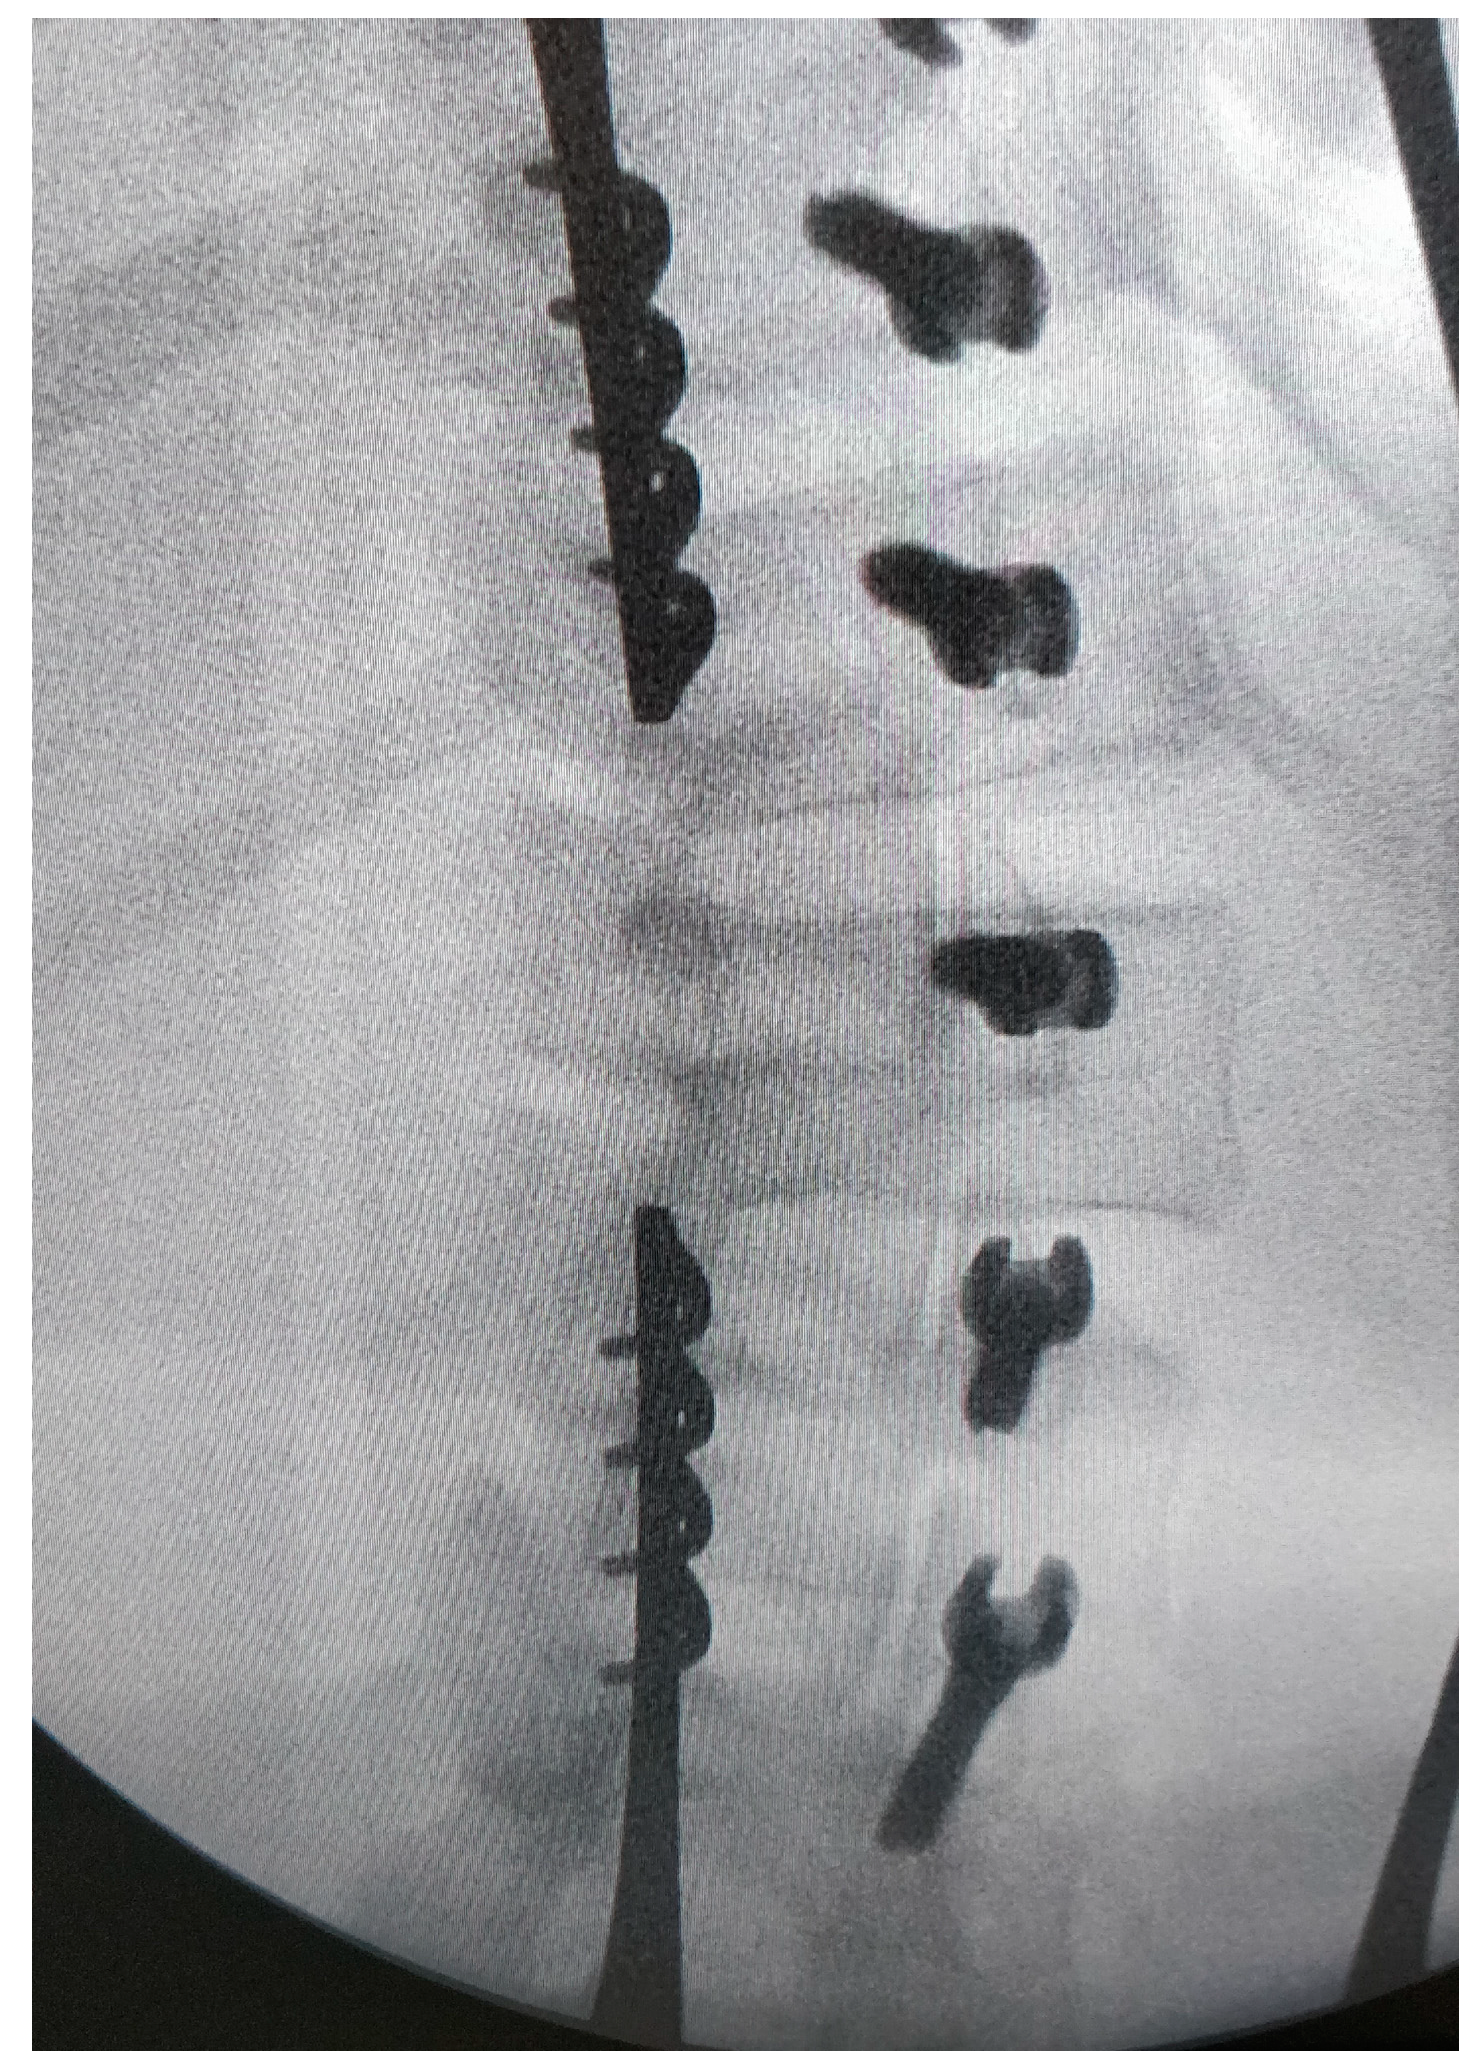

The chord is progressively placed within the screw heads from the cranial to the caudal end. Curve correction is performed with a combination of external manoeuvres (push on the convex side) and tension of the tether level by level using the appropriate tool (Figure 6).

Tightening of the cord: the device is placed against the screws to put tension in the cable, and then the bolt is tightened. The procedure is repeated for each level.

The material itself is also important. Screw breakage only occured with the CTJ+™ material from Neurofrance® and always on the proximal screw (Figure 8). Indeed, these screws had a very wide thread and a thin core, making them probably less strong for the same diameter. No breakage occurred with the Braive™ or the Reflect™ screws. Anyway, these breaks did not change the outcome of the concerned patients.

A 13-year-old female, Risser 2. The main curve measured 37° pre-operatively and −18° at 2 years. The overcorrection did not change the good result. In this case the secondary curve improve from 23° to 0°. Note also the broken screw.

We have seen that screw issues happened at the extremities (proximal and distal). Effectively, these screws are subjected to stress in only one direction, while for the others the forces are balanced on both sides. For this reason, now we suggest adding one more vertebrae proximally and distally to serve as an anchor for the real upper or lower vertebrae and to tighten the cable gently at those levels. For example, if a T11 to L3 correction is necessary, we suggest an instrumentation from T10 to L4 with a gentle tension between T10–T11 and L3–L4.